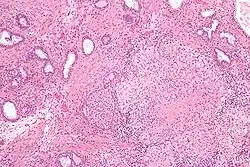

| Micrograph showing a granulomatous prostatitis due to BCG treatment for bladder cancer. H&E stain. | |

Noticeable destruction of Acini, surrounded by epitheloid cells, giant cells, lymphocytes, plasma cells and dense fibrosis.[2]